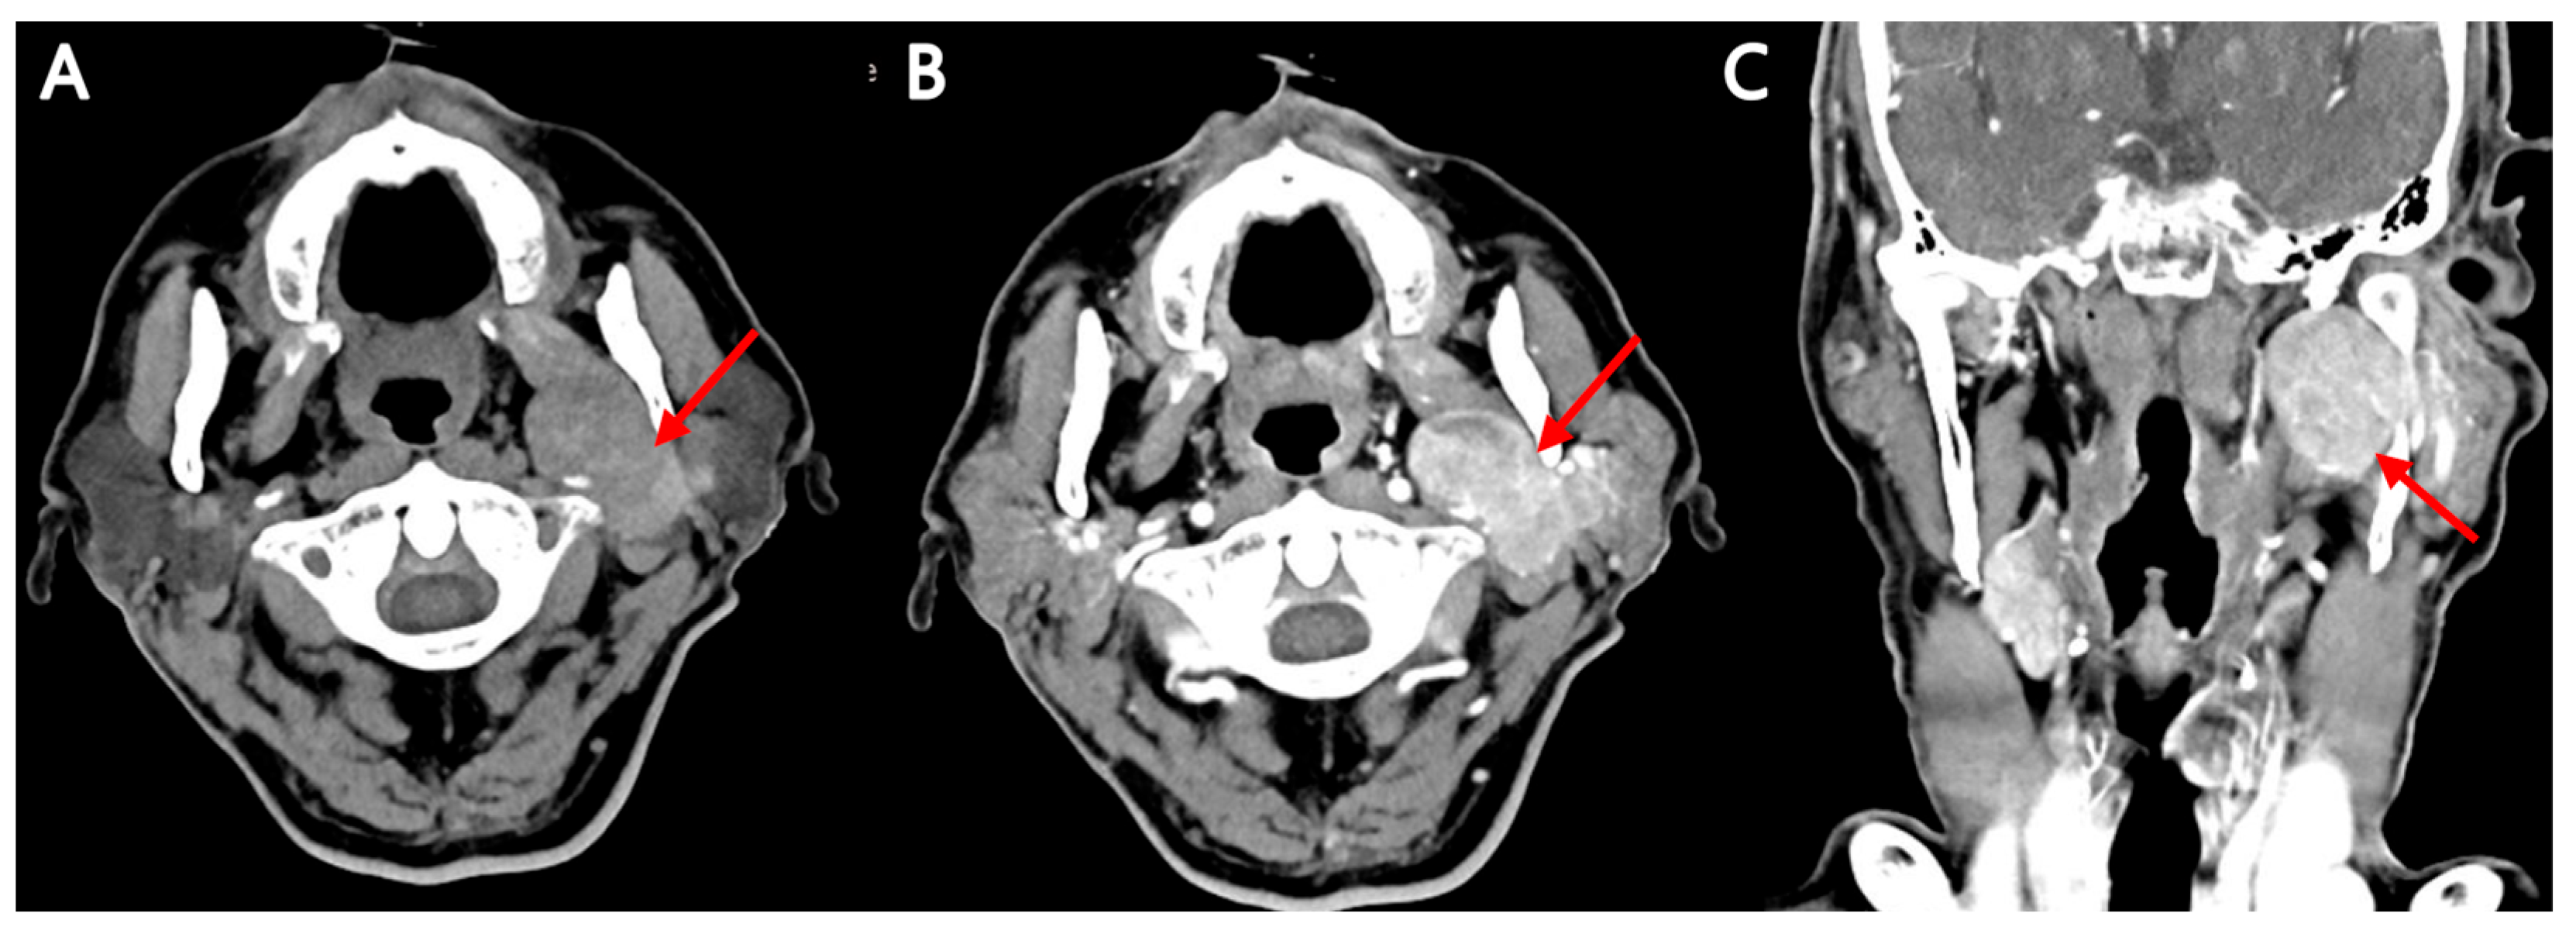

Multimodality Imaging of Warthin’s Tumor: PET/CT, Scintigraphy, MRI, and CT